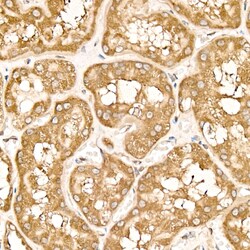

Invitrogen™ METTL4 Recombinant Rabbit Monoclonal Antibody (9N4K4)

| ELISA, Immunohistochemistry (Paraffin) | |